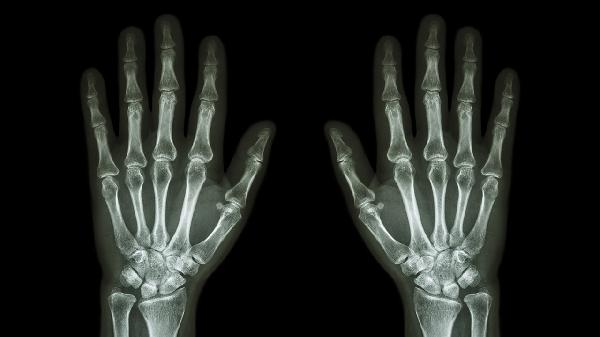

手指关节囊损伤后的功能怎么恢复

手指关节囊损伤后的功能恢复可通过制动保护、冷热敷交替、康复训练、药物治疗及手术治疗等方式改善。损伤通常由外伤、慢性劳损或炎症等因素引起,表现为疼痛、肿胀及活动受限。